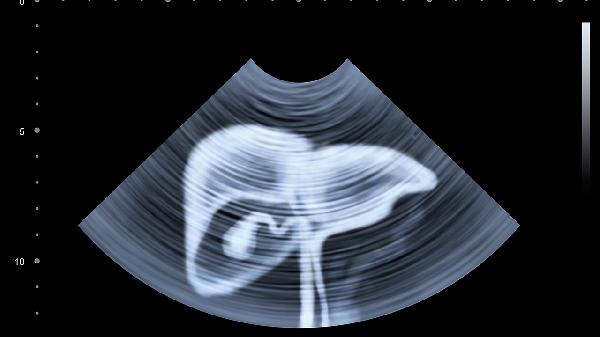

左侧腹部按压有疼痛感可能由多种原因引起,包括胃肠功能紊乱、结肠炎、胰腺炎、肾结石、女性生殖系统疾病等。建议及时就医,明确诊断。

三、胰腺炎

胰腺位于上腹部深处,其尾部延伸至左侧,因此急性或慢性胰腺炎均可引起左侧腹部,尤其是左上腹的持续性剧痛或压痛,疼痛常向背部放射。发病常与胆道疾病、大量饮酒、暴饮暴食有关。患者可能伴有恶心、呕吐、发热等症状。胰腺炎属于急重症,必须立即就医。治疗包括禁食、胃肠减压、静脉补液以让胰腺休息,并使用注射用生长抑素、注射用奥曲肽等药物抑制胰液分泌。疼痛剧烈时,医生会使用盐酸布桂嗪注射液等镇痛药物。恢复期饮食须严格遵循医嘱,从清流质开始逐步过渡,绝对禁止饮酒和高脂饮食。